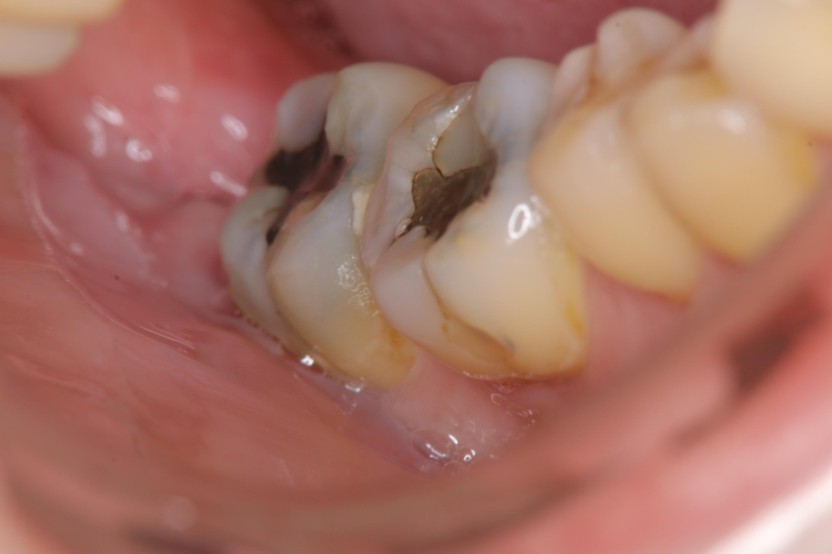

治療前,右下阻生齒造成牙周腫脹

治療前,環口X光,阻生齒